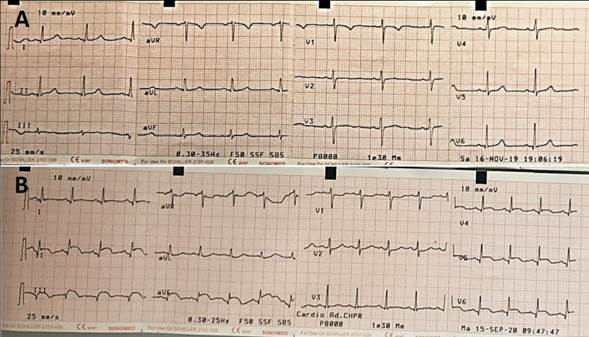

Mujer de 45 años, tabaquista, portadora de carcinoma epidermoide de cuello de útero diagnosticado hace 10 meses, recibe radioterapia (RT) y quimioterapia (QT). Instala dolor con características de organicidad sobre región pélvica y columna lumbar, por lo que se realiza resonancia magnética (RM) de abdomen y pelvis, que evidencia la presencia de una masa paravertebral lumbar derecha de aspecto maligno. Ingresa a sala de ginecotocología para analgesia reglada con antiinflamatorios no esteroideos y opiáceos y para biopsia diagnóstica de dicha tumoración. Asintomática en lo cardiovascular, se realiza electrocardiograma (ECG) de 2 derivaciones preoperatorio. Este evidencia: ritmo sinusal de 100 cpm, onda P normal, PR: 160 ms, EEM: + 30º, QRS de 80 ms de duración con supradesnivel ST en DII, DIII y aVF, V5 y V6 con infradesnivel ST en aVR, V1 y V2, QTc: 402 ms. El ECG de hace 10 meses era normal (figura 1).

Figura 1: A) ECG previo sin alteraciones. B) ECG posterior donde se destaca supradesnivel-ST inferolateral.

Reportamos el caso de una paciente joven, en estudio por una probable recidiva tumoral a nivel lumbar, que se presenta asintomática en lo cardiovascular, con un ECG que evidencia supradesnivel-ST localizado inferolateral. Se realizó diagnóstico posterior de sarcoma indiferenciado.

El manejo inicial de esta situación es complejo, ya que las alteraciones electrocardiográficas son indistinguibles de aquellas que ocurren por oclusión de un vaso epicárdico y puede desencadenar, como en este caso, una conducta intervencionista precoz. La evaluación no invasiva mediante varias modalidades de imagen (multimodal), cuando está disponible, podría ser la mejor forma de abordar estos casos, en los que la clínica no es acorde al ECG.

El hallazgo de una elevación del segmento ST como forma de presentación de las tumoraciones cardíacas es infrecuente y puede deberse a la compresión tumoral de una arteria coronaria o a la invasión miocárdica. Varios mecanismos a nivel celular podrían explicar la elevación persistente del segmento ST. Entre ellos, el desarrollo de una corriente de injuria secundaria a una reacción inflamatoria peritumoral; la transferencia iónica de potasio desde el tejido necrótico al miocardio adyacente lo que produce una diferencia de potencial eléctrico entre estas áreas; y, finalmente, el estiramiento de las fibras musculares adyacentes que llevan a una corriente de injuria similar a la que ocurre en el caso de los aneurismas ventriculares(2,3). En nuestro caso, la angiografía evidenció una disminución de calibre del ramo posterolateral, que podría corresponder a compresión tumoral extrínseca (figura 2). Sin embargo, no creemos que el supradesnivel-ST pueda explicarse por la compresión coronaria extrínseca. Dada la evolución electrocardiográfica, con persistencia del supradesnivel sin evolución a ondas Q y la ausencia de marcadores de necrosis miocárdica, no planteamos se trate de un cuadro de isquemia en curso. Sugiriendo fuertemente los hallazgos electrocardiográficos podrían ser secundarios a los mecanismos celulares inducidos por el tumor.